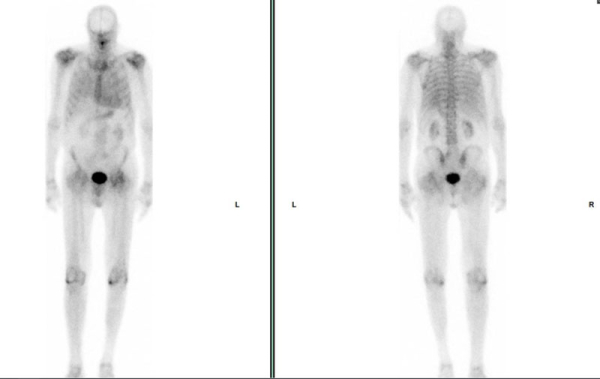

Scintigraphie osseuse à la recherche d’amylose cardiaque

Figure 13 : hyperfixation cardiaque supérieure à la fixation costale avec score Perugini = 2